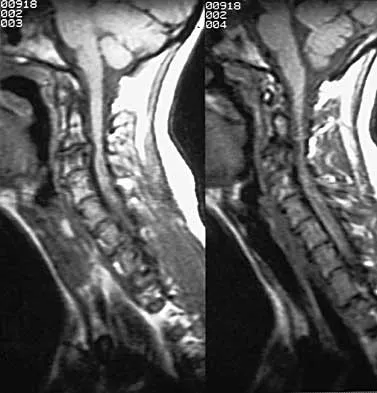

A 65-year-old man with ankylosing spondylitis has neck pain after falling back over his lawnmower, striking his thoracic spine, and forcing his neck into extension. Examination reveals subtle weakness of the intrinsics and finger flexors at approximately 4+/5. Initial management consists of immobilization in a rigid collar, and placing his head in the anatomic position. Radiographs reveal a subtle extension fracture of the lower cervical spine. Approximately 6 hours after the injury, he reports increasing paresthesias in his upper and lower extremities, and examination now shows his intrinsics are 2/5, finger flexors are 3/5, and his triceps are now weak at 4/5 on manual motor testing. In addition, his lower extremities now show weakness in both dorsal and plantar flexion of the ankle in the range of 4/5. Repeat radiographs appear unchanged. An MRI scan is shown in Figure 2. Management should now consist of

It is not uncommon for patients with ankylosing spondylitis to sustain extension-type fractures, most typically of the cervicothoracic junction. These fractures can appear nondisplaced or minimally displaced initially, making them difficult to diagnose. Because there is no mobility between vertebrae, fractures tend to occur more like those of a transverse fracture of a long bone. In addition, the vertebral bodies are vascular and their canals are relatively enclosed, making them vulnerable to epidural bleeding. The MRI scan reveals an epidural hematoma located posteriorly on the cord; therefore, the treatment of choice is surgical evacuation and a posterior laminectomy. Because of the intrinsic instability of such fractures at the time of the laminectomy, internal fixation and stabilization with a posterior fusion is warranted. A simple laminectomy will only increase instability, and control is unlikely with halo vest immobilization. An anterior procedure will not effectively treat the problem given the location of the hematoma. Consideration can be given to methylprednisolone and observation; however, this will not eradicate the problem. Bohlman HH: Acute fractures and dislocations of the cervical spine. J Bone Joint Surg Am 1979;61:1119-1142.